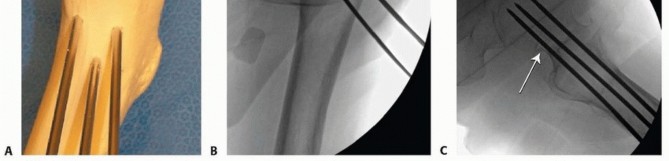

Once the position of the wires is verified in two planes by fluoroscopy, small (1 cm), full-depth incisions are made at each guide pin, and the soft tissues are spread to the bone. The lateral cortex may be drilled in patients with dense bone. Self-drilling, self-tapping cannulated screws are placed by power over the guidewires. Washers should be used in the more proximal, metaphyseal locations ( TECH FIG 1D,E). Screws should be long enough so that all screw threads are on the proximal (head) side of the fracture.

### TECH FIG 1 •

(continued)

D,E. Intraoperative fluoroscopic views demonstrating cannulated screw insertion over guidewires. D. AP view showing use of washers in this metaphyseal location. E. Lateral view showing parallel insertion and appropriate depth. A no. 15 blade on a long handle is positioned at the inferior margin of the base of the femoral neck on the AP fluoroscopic image. A small skin incision is made at this level, and the soft tissues are spread down to the joint capsule. With fluoroscopic verification of position, a small capsulotomy is performed to allow drainage of the hematoma from the capsule. A blunt sucker tip can be inserted through this small incision to evacuate any remaining hematoma.